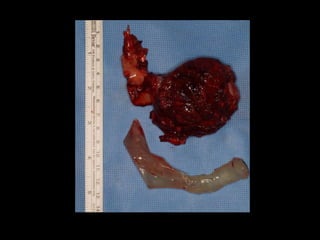

La oncología es una de nuestros mayores retos dentro de nuestra especialidad donde la cirugía ablativa y la cirugía reconstructiva se enfrentan. Cirugías de alto coste: para el paciente, el equipo quirúrgico, el hospital y el sistema sanitario. El acceso a biomodelos nos permitió la exploración de su uso y su utilidad.

La oncología esuna de nuestros mayores retos dentro de nuestra especialidad donde la cirugía ablativa y la cirugía reconstructiva se enfrentan. Cirugías de alto coste: para el paciente, el equipo quirúrgico, el hospital y el sistema sanitario. El acceso a biomodelos nos permitió la exploración de su uso y su utilidad.